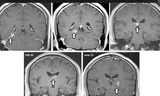

Các bác sĩ của bệnh viện Tân Hoa, Thượng Hải, Trung Quốc vừa phải tiến hành phẫu thuật loại bỏ một con sán dài 8 cm sống trong não một cậu bé 11 tuổi sau khi bị lên cơn động kinh.

Cậu bé được đưa tới bệnh viện hôm 12/11 sau khi bị lên cơn co giật và mất ý thức. Bố mẹ cậu cho biết có lẽ nguyên nhân của của việc này là do cậu bé ăn những thực phẩm mất vệ sinh hoặc chưa nấu chín trên đường phố như thịt nướng, thịt rắn...

Các bác sĩ xác định loại sán ký sinh trong não cậu bé là sparganosis, thâm nhập vào cơ thể người khi con người ăn phải thịt ếch, thịt rắn hay động vật có vú nhỏ đã bị nhiễm sán. Đôi khi loại sán này còn xuất hiện khi con người ăn phải thịt lợn sống, chưa được nấu chín.

Sán xâm nhập vào cơ thể thông qua đường tiêu hóa, lan tới mắt hoặc não, gây tổn thương cho não bộ.